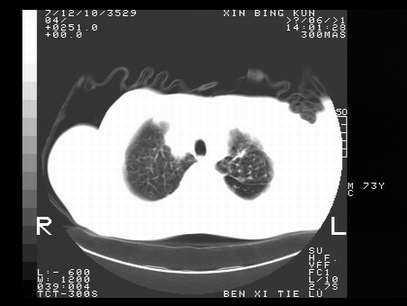

标题: CT10820:男,73岁,病史肺TB,现病史肺炎,直肠CA术后 [打印本页]

标题: CT10820:男,73岁,病史肺TB,现病史肺炎,直肠CA术后

双肺间质改变,依据病史双肺多发结节灶考虑转移,少量胸水.

1.两肺结核.2.两肺多发转移瘤.3右侧少量胸腔积液4.主动脉钙化.

双肺多发结节及条片状致密影,右侧少量胸腔积液。临床:直肠ca术后,肺tb病史。综合考虑:1 双肺转移!2 继发性肺结核合并感染!

此人病史较复杂,原有肺结核,直肠癌术后。肺部病灶形态亦呈多形性。因此,不可仅以一种病来解释肺部的病变。双肺多发的类圆形结节灶,结合病史还是首先考虑转移瘤,而双肺其余病灶还需结合化验室检查,结核或肺部感染在无其它检查资料的情况下不好排除。还是那句话----放射科医生不是开照像馆的,我们也是医生,看片一定要多结合临床及其它检查资料。要当一名合格的放射科医生,并不比当一名临床医生容易,我们可别把自已不当医生看。

两肺多发结节影,并见滋养动脉与其相连,考虑 两肺转移. 右侧胸腔积液考虑胸膜转移.

左肺上叶下叶背段,右肺中下叶见多发斑片状、条索状高密度影,兵变周围小结节影形成“树芽”样改变。 左肺上叶舌段近前胸壁处及右肺中叶内侧段见结节影。右侧胸膜腔内见液体密度区。纵隔内未见明确增大淋巴结。考虑左肺上叶舌段近前胸壁处及右肺中叶转移瘤可能性大。两肺继发型肺结核。右侧胸腔积液。